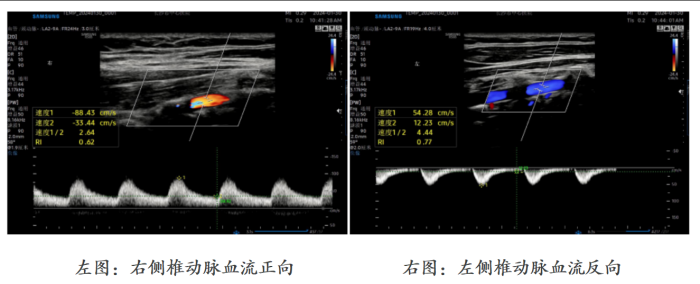

李玲表示,头晕并伴有左上肢无力、发凉的症状已出现近一年时间,她曾尝试多种理疗方法,但症状始终未见好转。近日,李玲到长沙市中心医院健康管理中心做体检,超声室医生胡婷发现她左侧椎动脉血流完全反向,同时左侧锁骨下动脉开口处存在狭窄。出于职业警觉性,胡婷医生立即带李玲去内科诊室测量了双臂血压,发现其左臂血压(106/65mmHg)显著低于右臂(126/75mmHg),差值超过20mmHg。结合经颅多普勒超声结果,高度怀疑她患上“锁骨下动脉盗血综合征”。李玲随即被转入神经内科,经脑血管造影等检查明确诊断后,接受了左侧锁骨下动脉球囊扩张术+左侧锁骨下动脉支架植入术,术后头晕症状已大幅改善。